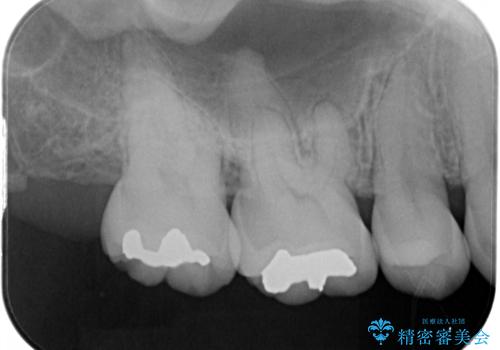

むし歯の治療。ゴールドインレーによる修復

- 定期健診にてむし歯を認めたためゴールドインレーにて治療を行いました。

拡大鏡で常に口腔内を診察しているため、小さなむし歯も見逃さずに治療を行っています。

ゴールドインレーは適合が良く、割れることもないため、長期的に安定した治療法となります。